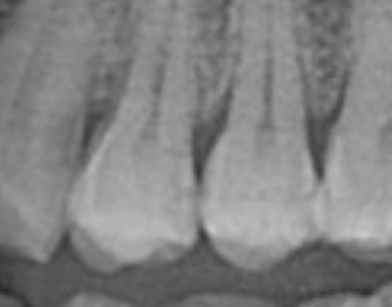

해당 치아 부분 인접면 충치있다고 두군데 세라믹 인레이 하였습니다.

• 1번 째 사진

일단 강xx 선생님의 개인 의견이 전체의 치과 의견을 대변하지 않습니다. 현재 사진으로는 충치 부위가 확실합니다. 다만 인접면이라면 부위는 다른 충치와 다른 점이 있습니다. 해당 부위로 바로 기구를 집어넣을 수 있는 방법이 전혀 없으며 위에서부터 해당 부위를 깍으면서 들어가야 합니다. 즉 치질 손상이 많을 수 밖에 없으며 대부분 인접면은 간단한 레진 등으로 수복할 수 있으나 수복 이후 시린 증상이 있어 대부분 치과에서 인레이를 많이 합니다.

즉 과잉 진료는 아니며 해당 부위에 아직까지 큰 통증이 없더라도 시간이 지나 신경까지 침범한다면 신경치료까지 이어질 수 있는 상황으로 보여집니다.

인접면에 충치가 있다면 일반적으로 인레이치료를 하게 됩니다. 치과의사마다 생각이 다르기 때문에 레진으로 하시는 분들도 계시고 인레이를 하는 선생님도 계십니다. 저도 저정도 우식이면 인레이치료를 할것같습니다.

사진으로 봤을 경우에는 인접면에 충치가 있어보입니다. 범위가 어느정도인지는 육안으로 확인하지 않는한 정확하게 알수는 없어요.